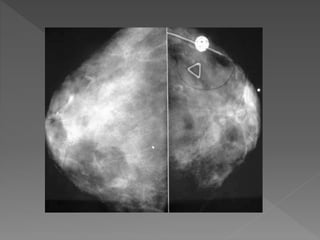

 49 AÑOS

 MAMOGRAFIA DE CONTROL

 MICROCALCIFICACIONES AMORFAS

 CARCINOMA DUCTAL IN SITU

 TIPO CRIBIFORME

 12 mm

 BAJO GRADO

 CON COMEDO NECROSIS

 MARGEN 10 mm

Dr. S Ralon

USC/VNPI 6

EXCISION O CIRUGIA

CONSERVADORA

MAS TAMOXIFEN

S. Ralon